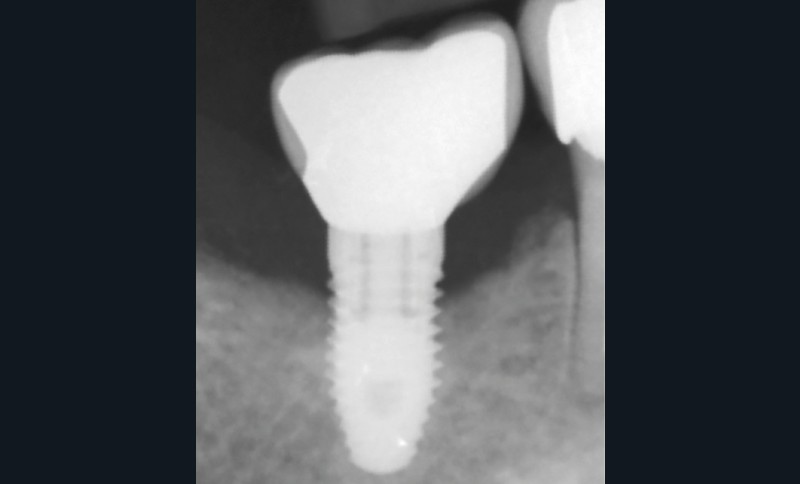

Soins péri-implantaires et parodontaux de soutien

La patiente est restée 4 semaines sans couronne. Après l’intervention chirurgicale, elle a entamé un programme de soins péri-implantaires et parodontaux, avec des visites de rappel tous les 4 mois.

Conclusions

Dans les cas de traitement de péri-implantite, un suivi d’un an est considéré comme un suivi court. Néanmoins, le cas présent est stable après un an et ne présente aucun signe de récidive. Des contrôles supplémentaires sont nécessaires.